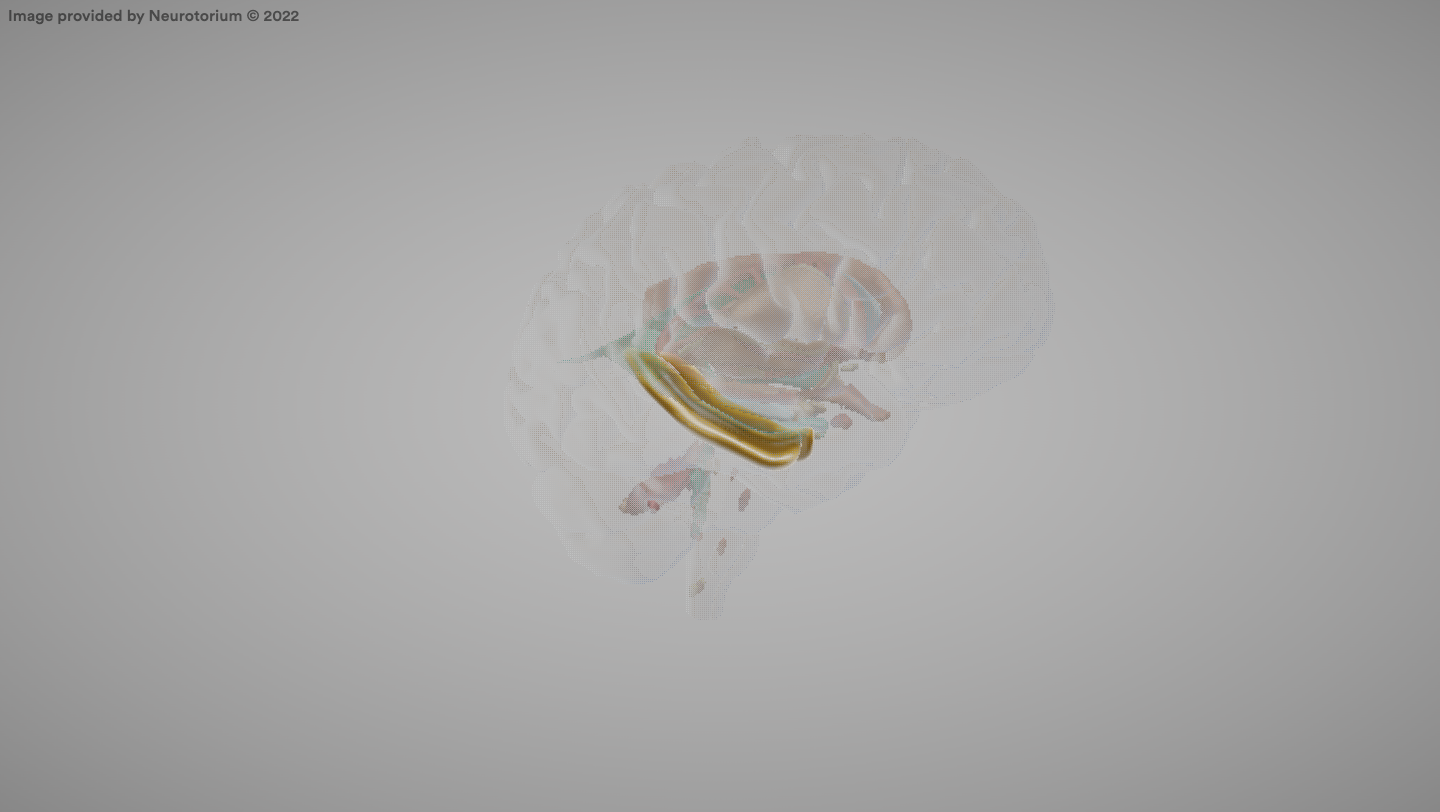

Cerebellum

A brain structure that coordinates movement and balance.

Pons

A part of the brainstem involved in motor control and sensory analysis.

Medulla

The part of the hindbrain that controls vital functions like breathing and heart rate.